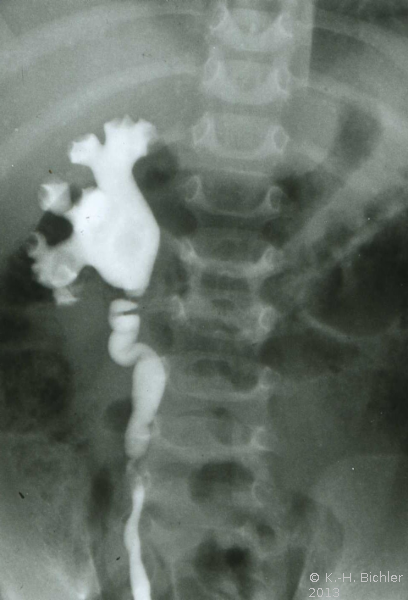

Ausgehend von einem Flankenschnitt (Intercostal) Freilegung des Nierenbeckens und Darstellung der Ureterabgangs (Engstellung, Taillierung), Resektion des Nierenbeckens und der Harnleiterengstelle. Naht des spatulierten Harnleiters an das resizierte und mit Naht verschlossene Nierenbecken (Abbildung HG1).